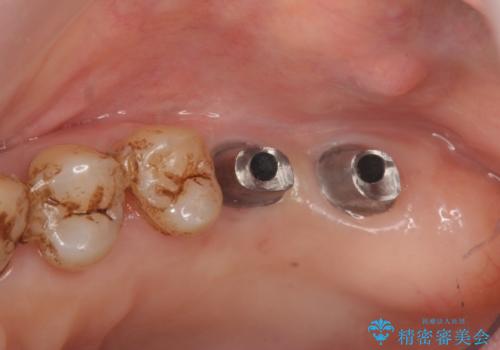

歯周病に対する全体治療

残すことのできない歯は抜去したのち骨造成を含めたインプラント治療を行い、しっかりとした咬合関係を確立していきます。

治療期間はかかりましたが、しっかりと歯周病治療・インプラント治療を行ったおかげで歯周病の状態は非常に良くなり、安定した咬合関係を確立することができました。